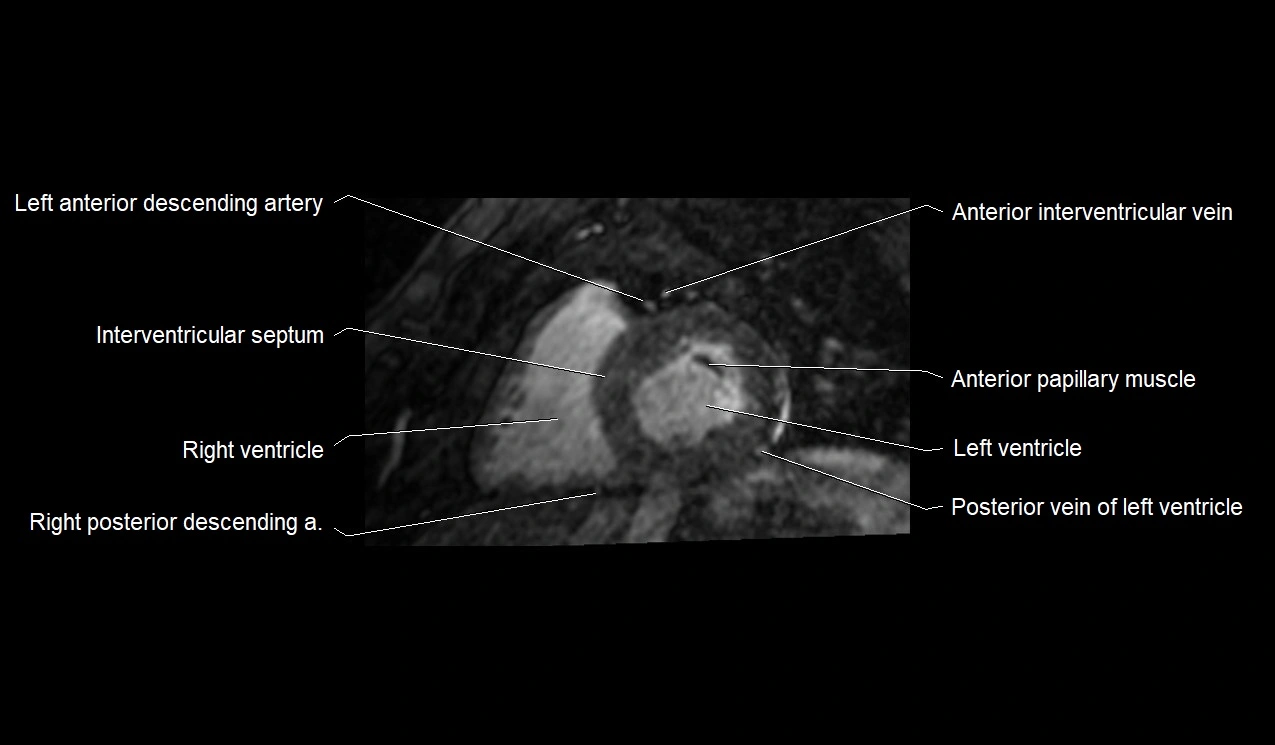

MRI image